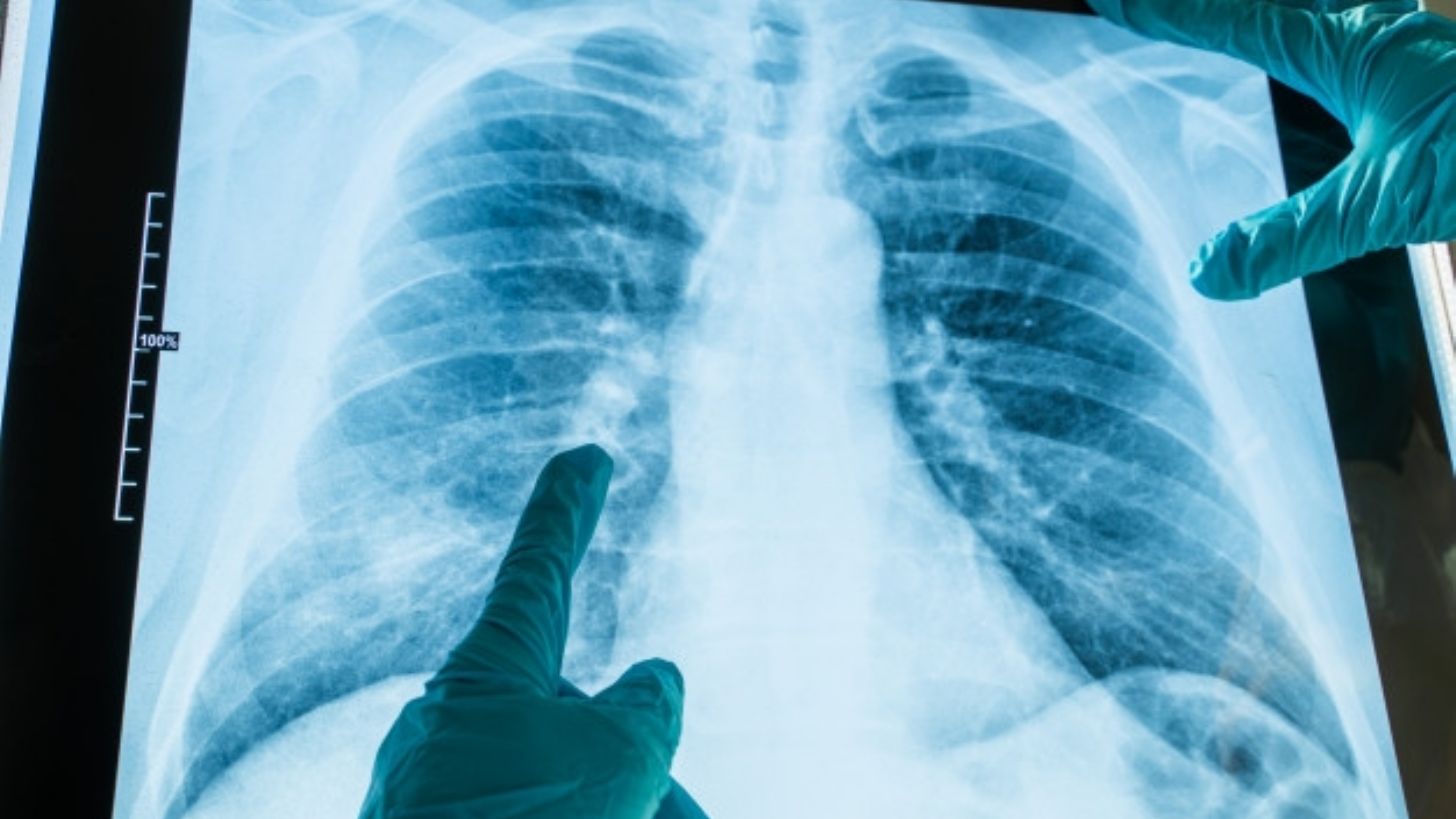

Argentina.- No es ningún secreto que la neumonía puede convertirse en una secuela causada por el Covid-19, sin embargo, recientemente se ha descubierto que el virus puede provocar otra versión de esta enfermedad en los pulmones calificada como bilateral.

A diferencia de la neumonía clásica, este nuevo tipo es mucho más grave y aún no se conoce a ciencia cierta todos los efectos que puede causar en el funcionamiento de los pulmones, pero los expertos creen que podría ser mortal, según sea el desarrollo de la infección por coronavirus.

De acuerdo con expertos del Sanatorio Delta de la ciudad de Rosario, en Argentina, la neumonía bilateral se trata de una especie de taponamiento que detiene la circulación del oxígeno.

Los especialistas aseguran que el 80 por ciento de las hospitalizaciones por SARS-CoV-2 tienen este tipo de complicaciones que se relación directamente con el daño a las células sanas causado por la presencia del virus.

Afortunadamente si es identificada y tratada a tiempo, los pacientes pueden recibir terapias de oxígeno que los ayude a respirar mejor, mientras el resto del cuerpo comienza a ser atendido por los especialistas para disminuir el impacto de la infección.